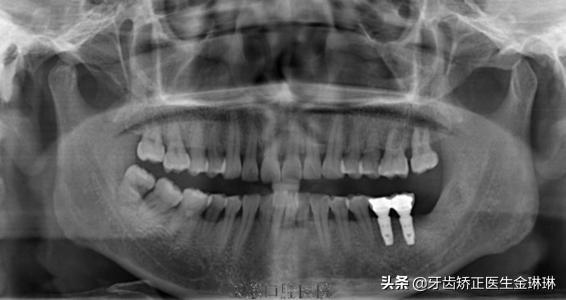

臨床上開(kāi)展種植技術(shù)需要配備較高的設(shè)備環(huán)境,例如大型X線診斷設(shè)備、臨床手術(shù)設(shè)備、技工設(shè)備、手術(shù)支持設(shè)備以及制作時(shí)需要的一些獨(dú)特的較貴重的種植牙修復(fù)材料。

種植牙手術(shù)前醫(yī)生要為缺牙者拍攝X光片、CT片,檢查牙齒的缺失情況確定調(diào)節(jié)方案,同時(shí),還需測(cè)量缺牙者的血壓、血糖等體征指標(biāo)來(lái)掌握患者身體情況;手術(shù)后密切觀察缺牙者的術(shù)后反應(yīng)及跟進(jìn)控制。